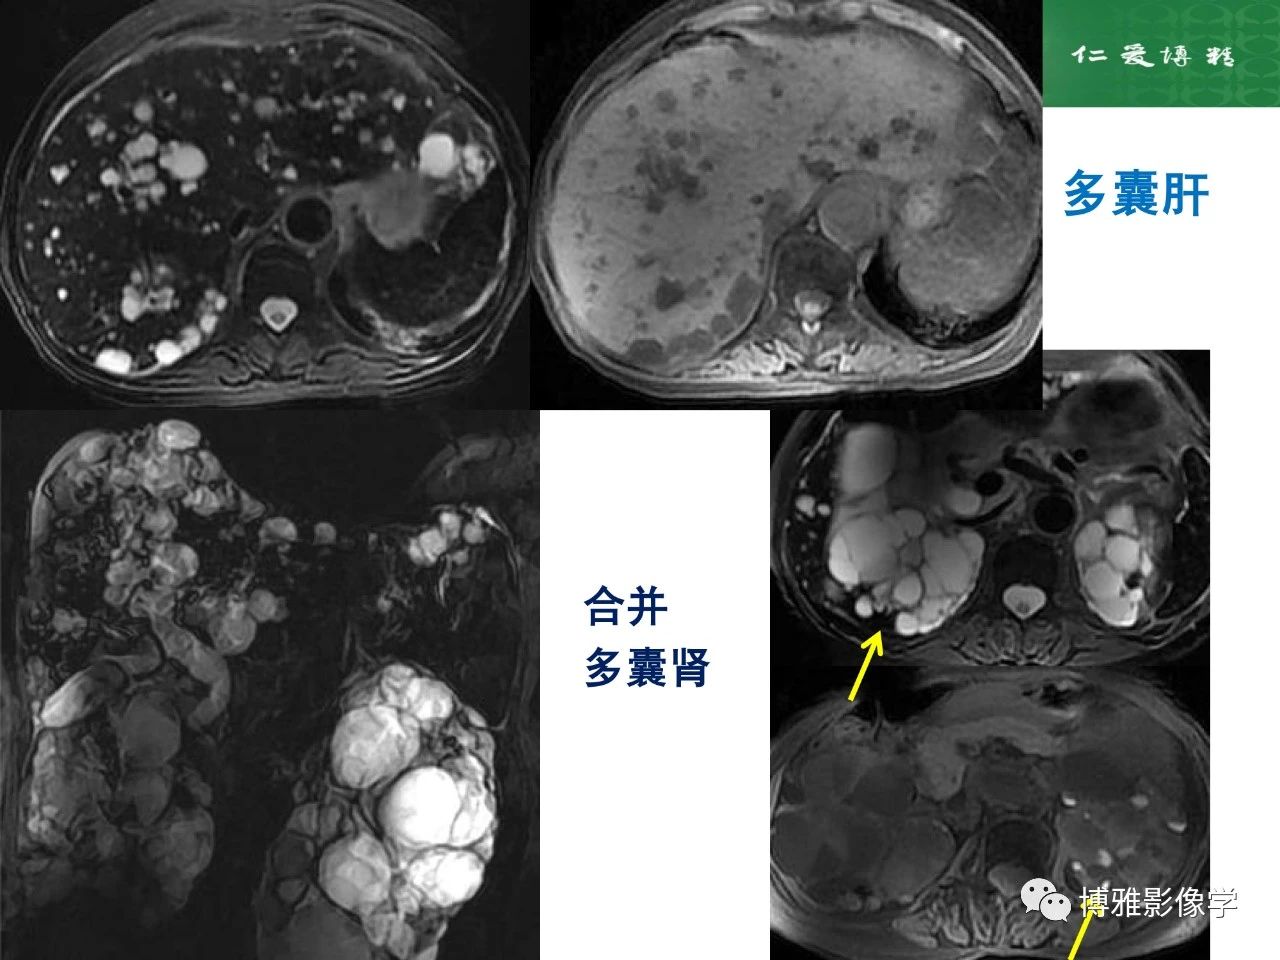

肝脏囊性病变的影像诊断思路